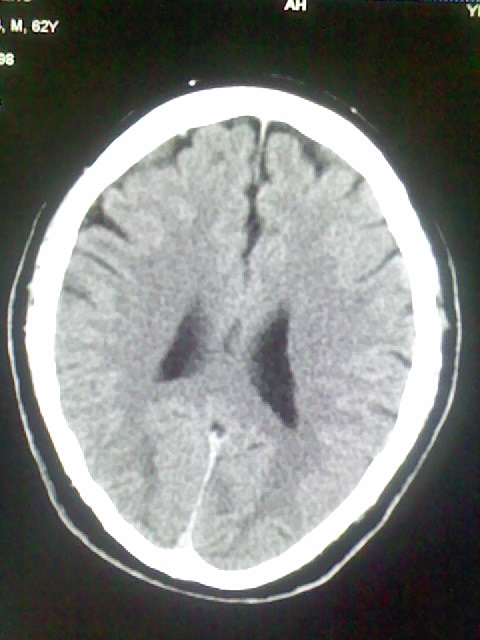

标题: CT15555:头痛 10余日 来诊大家帮忙看看

脑萎缩

脑沟、裂增宽,提法脑萎缩,建议mt检查。

脑萎缩,以小脑为著。

脑沟、裂增宽,提示脑萎缩

老年脑

支持轻度脑萎缩。